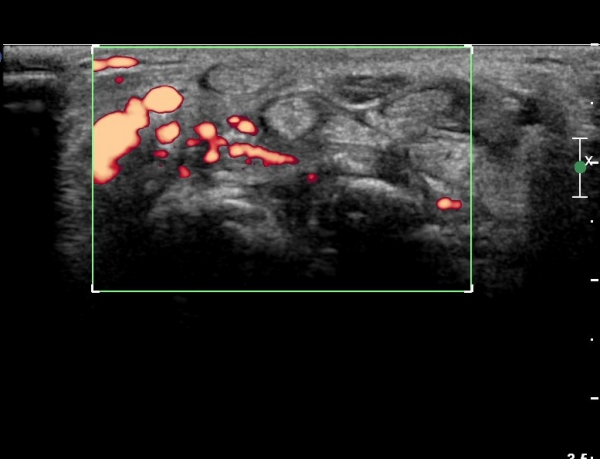

¼ö±Ù°ü ±ÙÀ§ºÎ Ⱦ´Ü¸é°Ë»ç¿¡¼ ±¼°î°Ç ½ÉºÎ¿¡ ¼®È¸È¼º À½¿µÀÌ Á¸ÀçÇϰí Àü¹ÝÀûÀÎ ¼öÁö ±¼°î°ÇÀÇ ºñÈÄ, Á¤Á߽ŰæÀÇ ºÎÁ¾°ú

ÈûÁÙ ¹× Á¤Á߽ŰæÀÇ Ç¥ÃþÀ¸·Î ÀüÀ§°¡ °üÂûµÈ´Ù, (»çÁø 3, 4,).